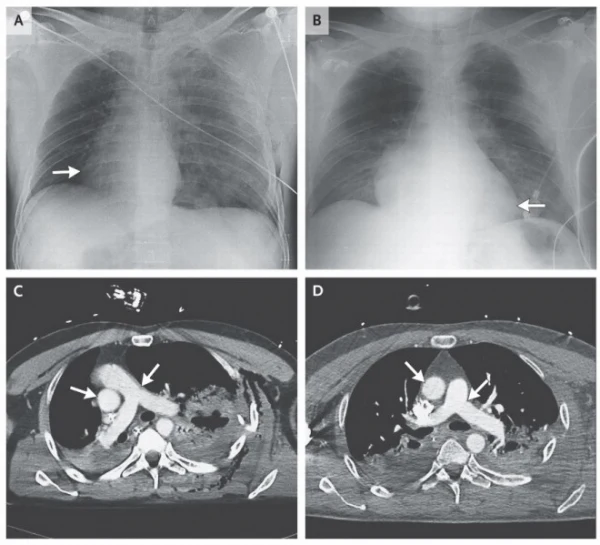

Lekarze byli zdziwieni, gdyż osłuchiwanie i badanie EKG sugerowały typową dekstrokardię. Właśnie tym medycznym terminem określa się sytuację, gdy serce znajduje się po prawej stronie klatki piersiowej. Jeżeli towarzyszy mu nieprawidłowe położenie innych narządów w obrębie klatki piersiowej i jamy brzusznej, mówimy o odwróceniu trzewi. Tutaj jednak nic takiego nie miało miejsca.Dopiero RTG klatki piersiowej i tomografia wykazały prawdziwą przyczynę przemieszczenia organu - lewostronną odmę prężną. W jej wyniku powietrze gromadzące się w jamie opłucnej sprawiło, że serce obróciło się o 90 stopni w prawo.Pacjent w wyniku wypadku doznał stłuczenia płuc i złamania żeber. Na tomogramie można było zauważyć prawostronną rotację aorty, pnia płucnego i przedsionków. 48-latkowi usunięto uszkodzoną śledzionę i przeprowadzono lewostronny drenaż opłucnowy. W dobę po zabiegu, serce pacjenta wróciło na prawidłowe miejsce.